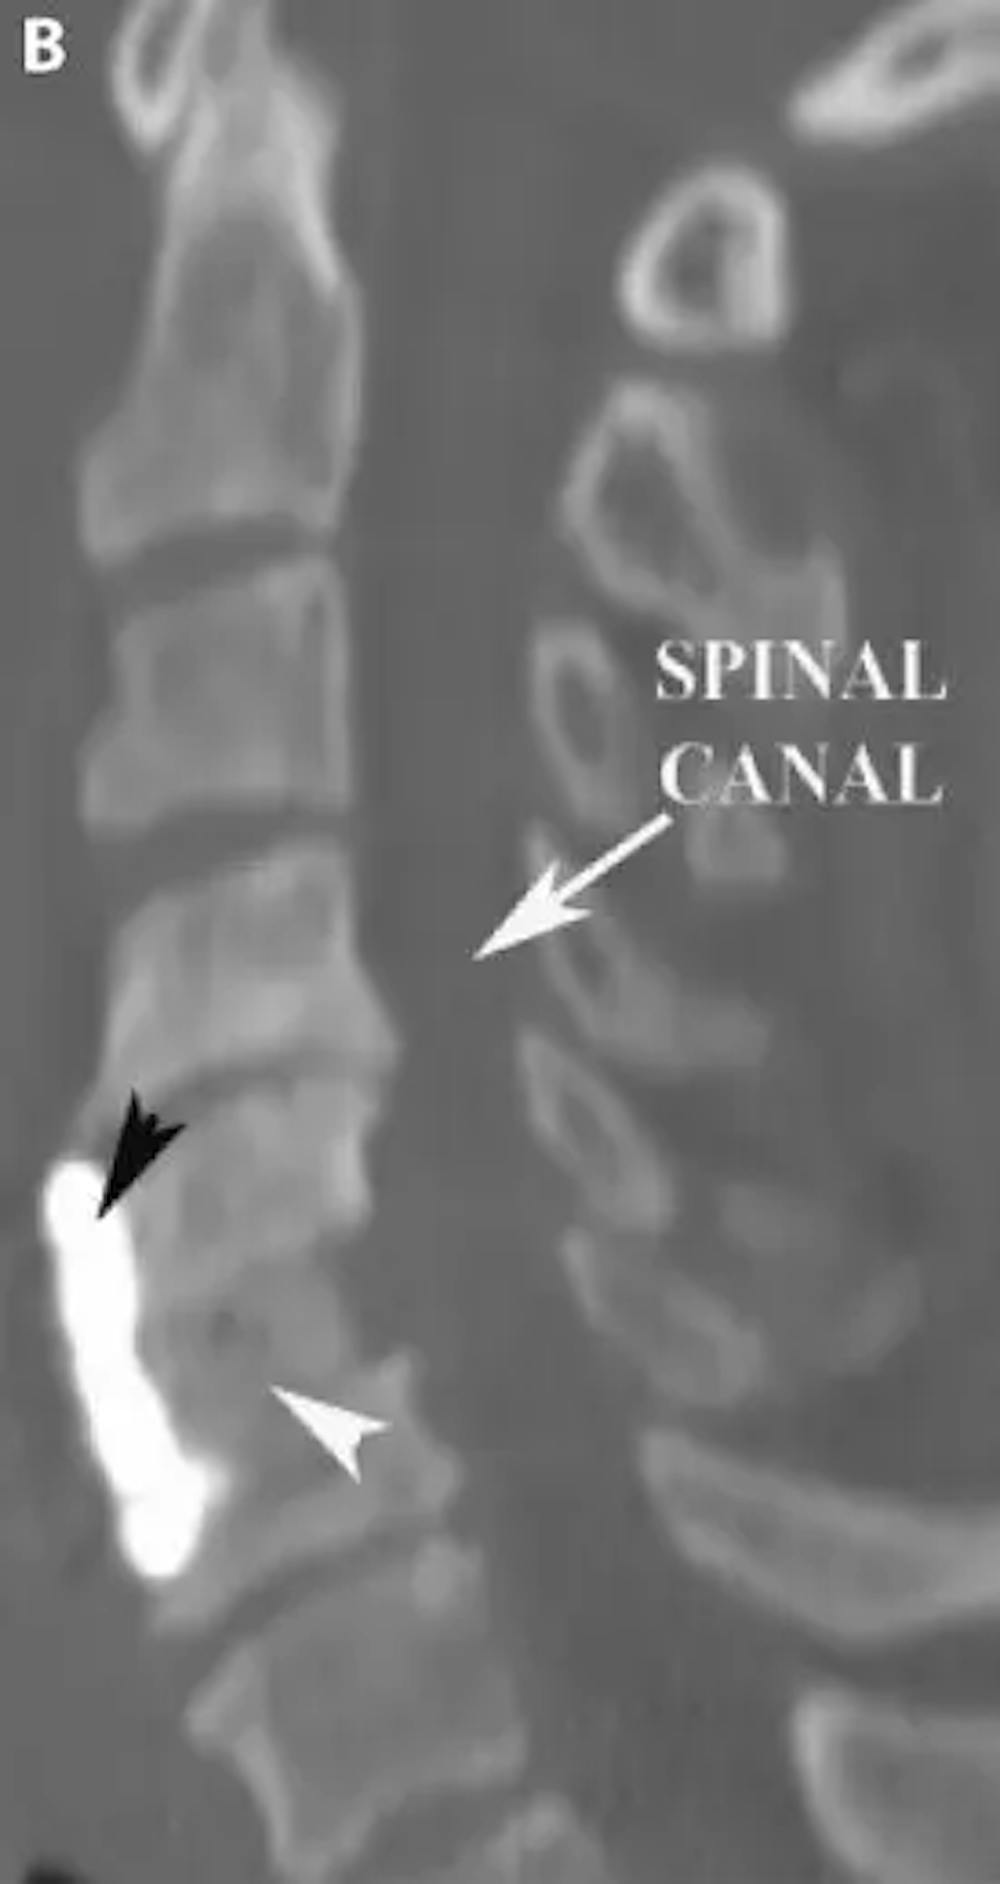

B) TC sagital postoperatoria de la columna cervical que demuestra una discectomía cervical anterior y fusión (DCA). Se coloca un injerto óseo (punta de flecha blanca) en el espacio discal vacío y se coloca una placa (punta de flecha negra) en la parte delantera de la columna vertebral para mantener el injerto óseo en su sitio

Muchos de los síntomas asociados a las hernias de disco cervical se resuelven sin necesidad de cirugía. La intervención quirúrgica suele reservarse para el dolor intenso que no responde a la terapia médica, la debilidad grave y los síntomas mielopáticos derivados de la compresión de la médula espinal. Las opciones quirúrgicas incluyen la discectomía y fusión cervical anterior (DCAF) de uno o varios niveles, la extracción de un cuerpo vertebral cervical (corpectomía) y la foraminotomía y discectomía cervical. Algunos pacientes con enfermedad discal cervical de un solo nivel pueden incluso ser candidatos a la colocación de un disco cervical artificial. El enfoque quirúrgico se determina de forma individual, teniendo en cuenta tanto la anatomía como la sintomatología del paciente.